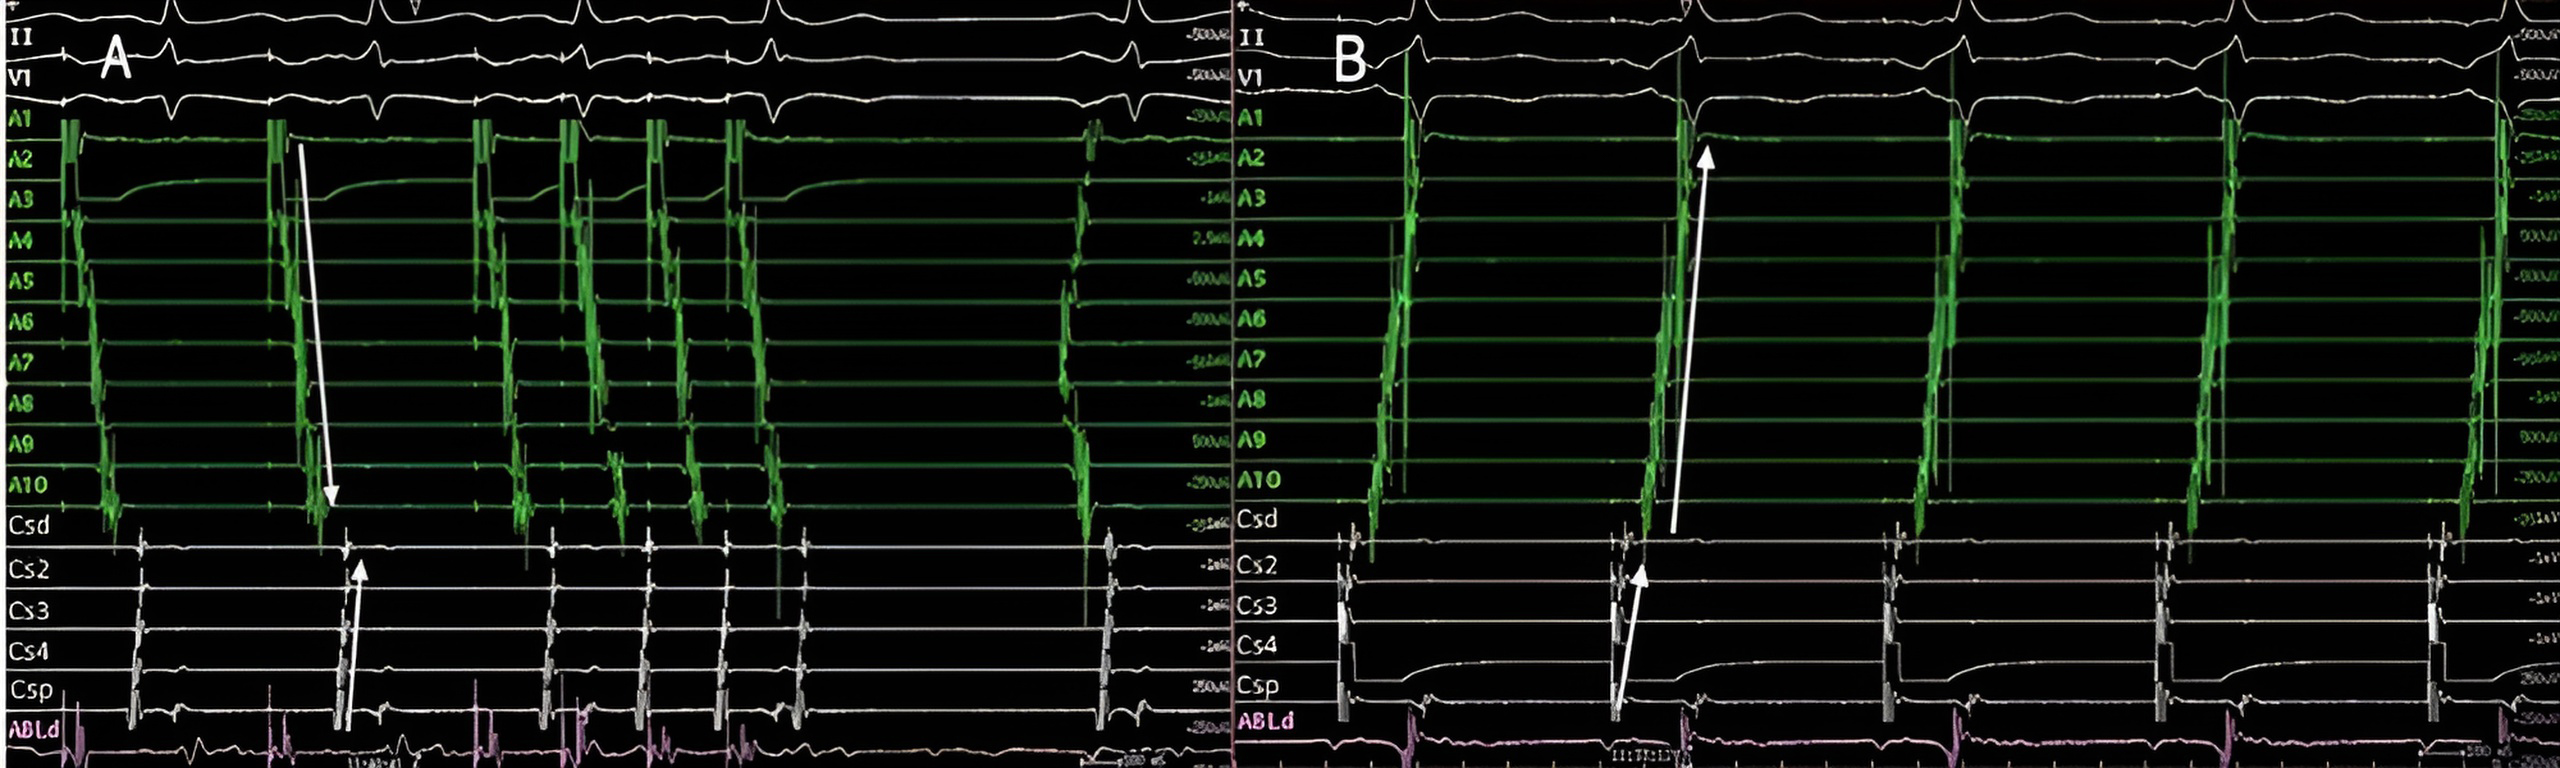

To confirm counterclockwise CTI block, pacing is performed from one of the dipoles of the duodecapolar catheter located on the lateral part of the CTI or directly with the ablation catheter (Fig. 13A). Conversely, to confirm clockwise CTI block, pacing is performed from the ostium of the coronary sinus (Fig. 13B). It is important to use relatively slow pacing frequencies to avoid rate-dependent CTI block [147].

Fig. 13.CTI block and non-inducibility evaluation. (A) Pacing from the low anterolateral right atrium (dipole A1) demonstrating ICT clockwise block. Activation of the RA is performed along the tricuspid annulus (A1-A10) until it reaches proximal coronary sinus (CSp). The administration of 3 extrastimuli does not induce any tachycardia. (B) Pacing from the coronary sinus os reaches the inferior septum (A10) and the activation wavefront is propagated toward A10-A1, demonstrating CTI counterclockwise block. CTI, cavotricuspid isthmus; RA, right atrium.